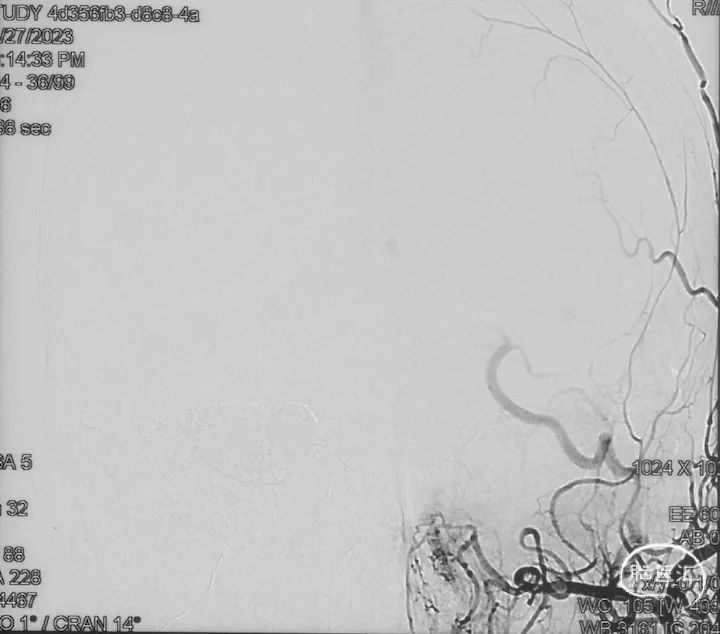

影像学的随访

术后9m

右侧颈内动脉造影未见瘘口显影及静脉早显

右侧颈外动脉造影未见瘘口显影及静脉早显

左侧椎动脉造影未见瘘口显影及静脉早显